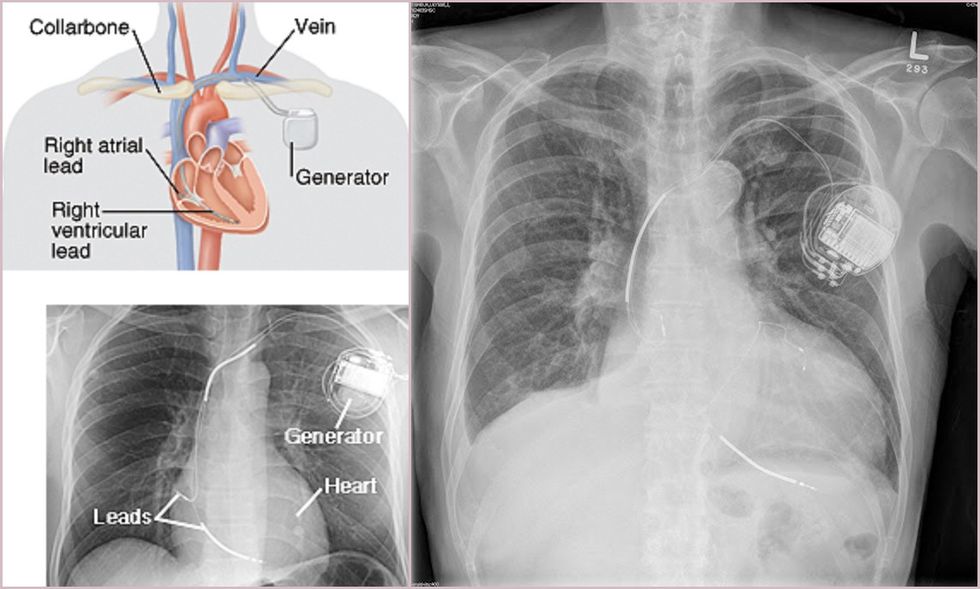

ICD-ja vendoset nën lëkurë, zakonisht në hapësirën menjëherë nën klavikulë për t’i monitoruar rrahjet e zemrës. Disa tela të hollë e lidhin ICD-në me zemrën dhe gjatë gjithë kohës kontrollohen të rrahurat dhe ritmi i zemrës. Monitorimi i zemrës realizohet përmes elektrodave.

ICD futet menjëherë nën klavikulë. Ngjan me një ‘pacemaker’ (stimulues kardiak) dhe është pakëz më i madh se një kuti shkrepëseje.

Defibrilatori kardioverter i implantueshëm përbëhet nga:

Gjeneratori i impulsit - një qark elektronik me bateri.

Një ose më shumë tuba elektrodash, të cilat vendosen në zemrën tuaj përmes një vene.